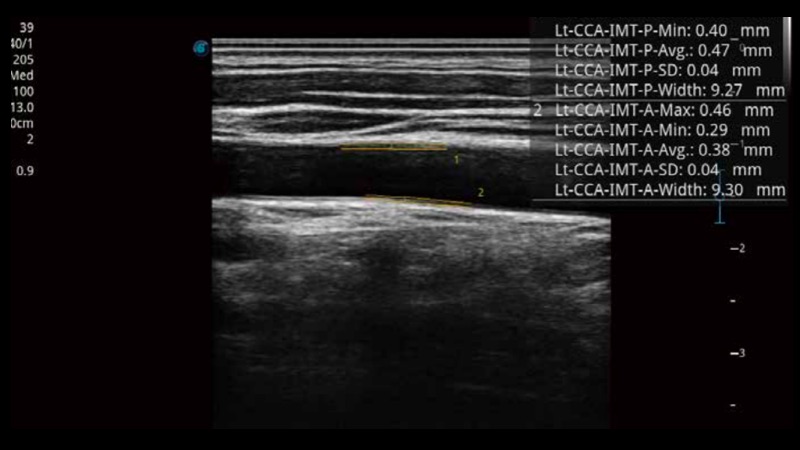

自動識別前后壁內(nèi)膜厚度,為心血管疾病早期評估提供快速準(zhǔn)確依據(jù)。